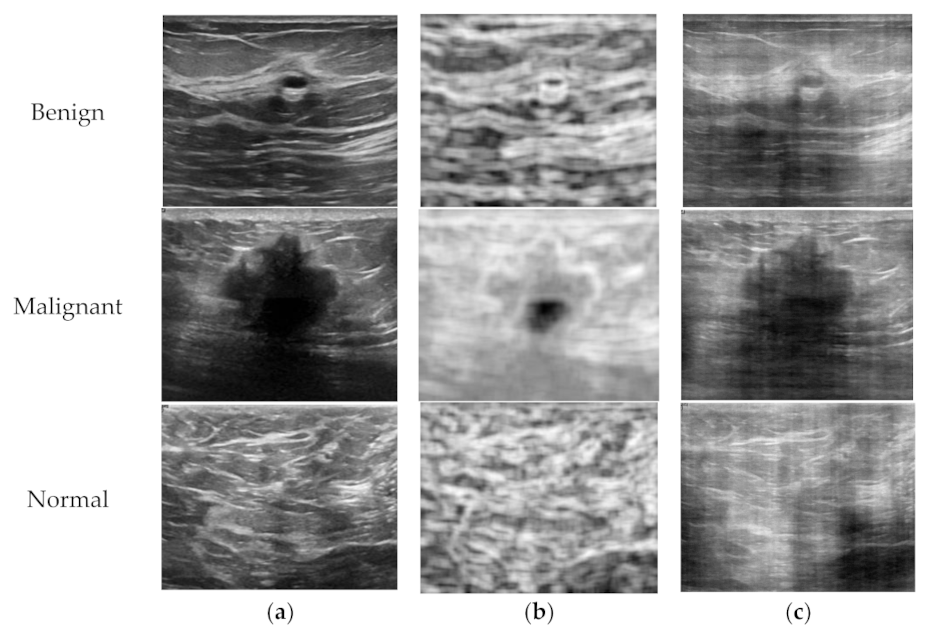

Although US imaging is one of the most popular modalities in practical clinical applications, it is difficult to find publicly available US image datasets in the literature. The dataset used in this study was recently released to the public, which consists of breast US images from 600 female patients aged between 25 and 75 years at the Baheya hospital in 2018 [15]. The data were acquired using the LOGIQ E9 ultrasound system and LOGIQ E9 Agile ultrasound system with the ML6-15-D matrix linear transducer, and converted gray scale images were obtained with an average size of 500 × 500 in PNG file format. The dataset consists of 780 B-mode images with pathological status and is categorized into three classes: normal, benign, and malignant. The numbers of images for the three classes are presented in Table 1, and the sample US images of each class are shown in Figure 1.

Figure 1. Sample B-mode images of the breast ultrasounddataset [11]; (a) Normal, (b) benign, and (c) malignant.

Figure 2. Sample B-mode, entropy, and phase images for a patient in each class; (a) B-mode images, (b) entropy images, and (c) phase images.